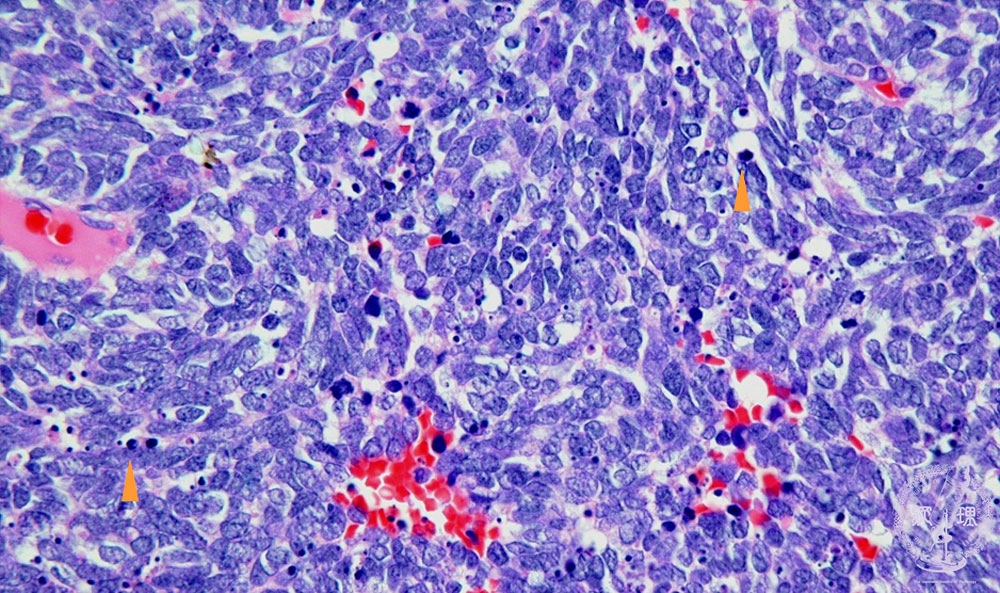

- ★(18)Small cell carcinoma

Microscopic view (HE stain, high power view): Small cell carcinoma of lung. Carcinoma cells have scant cytoplasm and a high N/C ratio. Many mitotic (arrow) and apoptotic (arrow head) figures are seen indicating high proliferative activity.